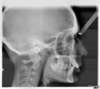

Téléradio